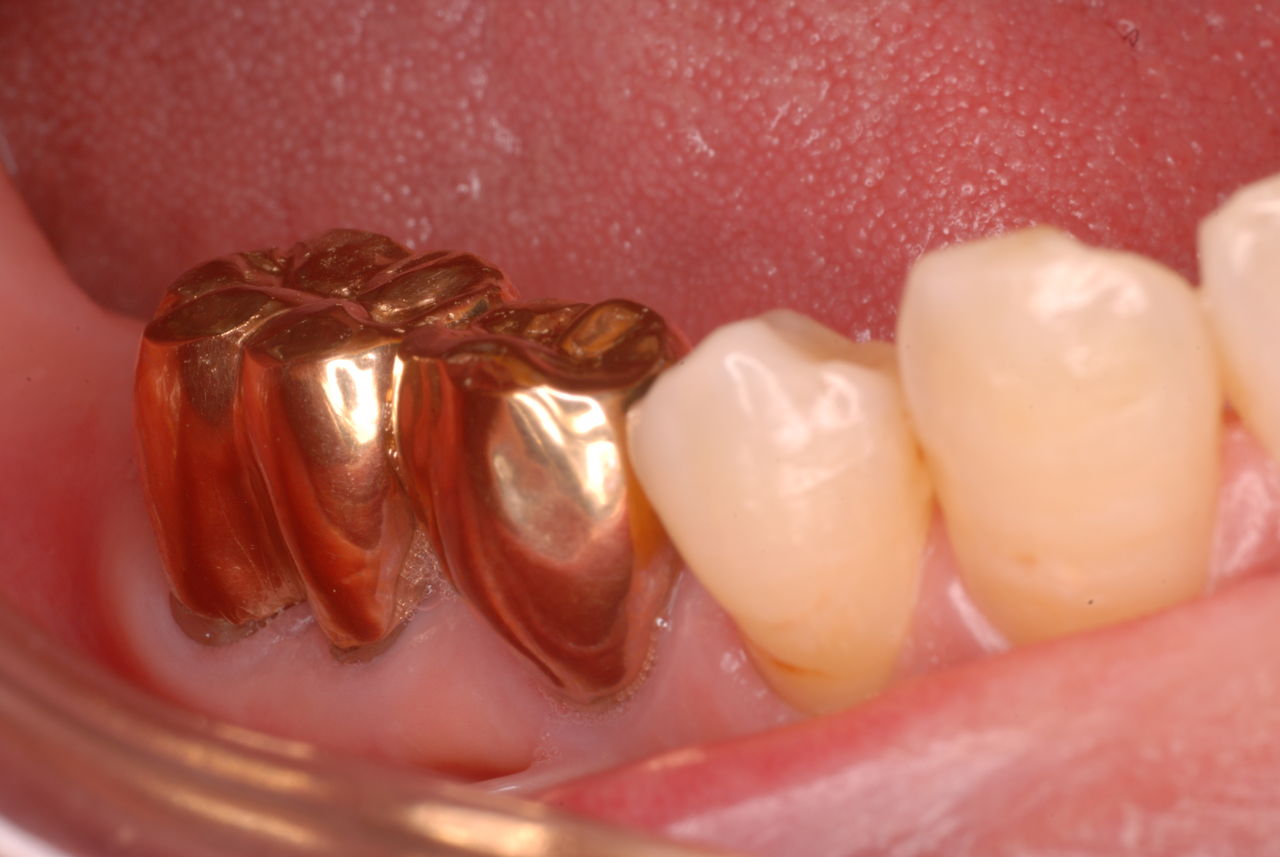

入れ歯の話から入りました。色々不満で注文があるようです。でも話が一段落して口腔内を調べると殆どの歯が重症で抜けそうな歯だらけなのです。

なぜ病気になるのかわからない方が多すぎます。歯が抜けるのは病気だからです。病気を治さずに何かお口の中に入れても土台である歯が抜けてしまっては同じことなのです。

何故歯が悪くなるのか、歯周病で抜けるのか分からなければ何を入れても歯は悪くなり抜けていくのです。

病気を治しましょう。それから差し歯や入れ歯を入れましょう!物を入れれば入れるほど、磨き方や掃除の仕方が上手にならなければ、すぐ抜けてくるのです。